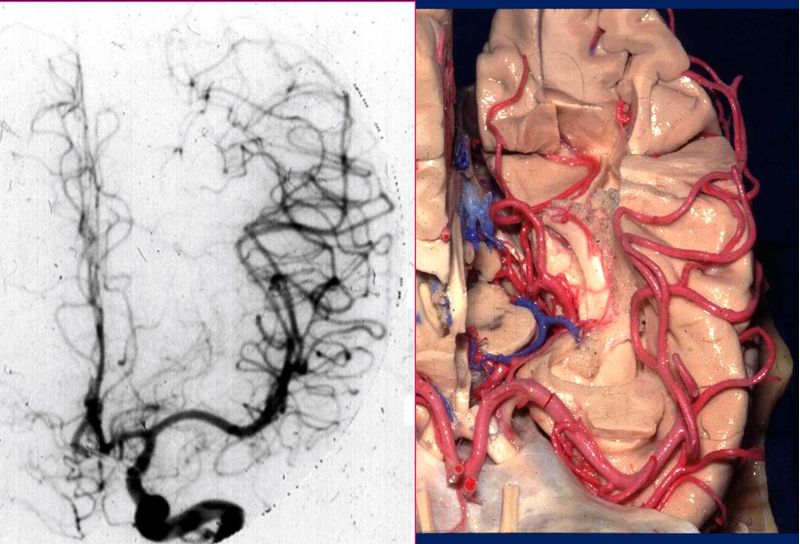

Ce cours vise à fournir un aperçu actualisé de l'anatomie microchirurgicale du cerveau, en mettant l'accent sur son application aux chirurgies des gliomes, des anévrismes

).Tout au long du cours, des cas cliniques et des vidéos de chirurgies respectives seront présentés pour illustrer l'application pratique de l'anatomie étudiée